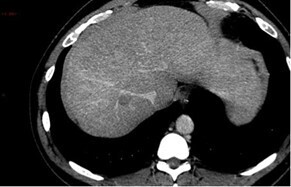

Le scanner ci-dessous est réalisé.

Question 3 - Dans les coupes précédentes, quelles sont les structures désignées par les flèches ?

Veine cave inférieure.

Corps vertébral.

Voies veineuses de dérivation péri-gastriques.

Question 4 - Vous constatez (une ou plusieurs réponses exactes) :

Non pas du foie gauche (= lobe gauche + segment IV) mais du lobe gauche (segments II et III).

Flèche verte.

La dysmorphie hépatique est caractérisée par une hypertrophie de segment I (en arrière du tronc porte et en avant de la veine cave inférieure) et du lobe gauche (segments II et III situés à gauche de la veine hépatique gauche) ; ainsi que par une hypotrophie du segment IV (situé entre les veines hépatiques gauche et médiane, séparé du lobe gauche par le plan passant par la veine hépatique gauche et le ligament rond). Peut également s’y associer une hypotrophie du secteur postérieur du lobe droit (segments VI et VII).

Pour la segmentation hépatique, voir la figure ci-dessous : On retrouve comme autre signe d’hépatopathie chronique les contours bosselés.

Les signes d’hypertension portale visibles en scanner sont :

– les voies veineuses de dérivation porto-systémiques (spléno-rénales, gastro-rénales, mésentériques, rétro-péritonéales…) ;

– la splénomégalie.